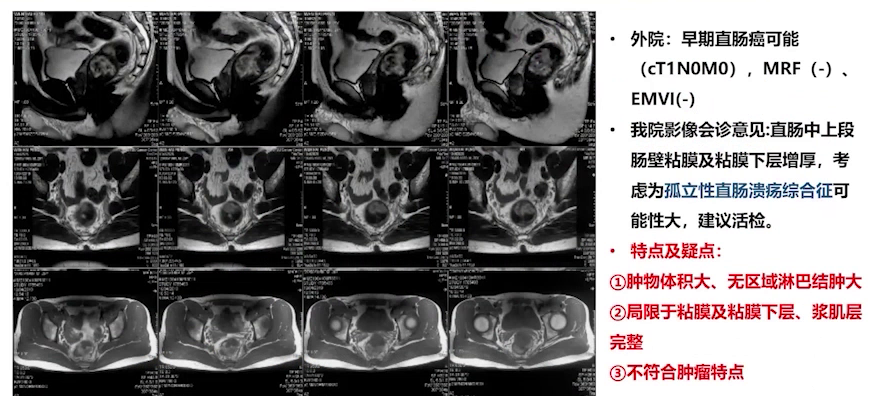

③胸部+腹部CT、盆腔MRI:提示早期直肠癌可能(cT1N0M10),MRF(-),EMVI (-)。

③盆腔MRI:肿物体积大,无区域淋巴结肿大,病变局限于黏膜和黏膜下层,浆膜层与固有肌层完整,不符合恶性肿瘤特点,诊断意见为孤立性直肠溃疡综合征。